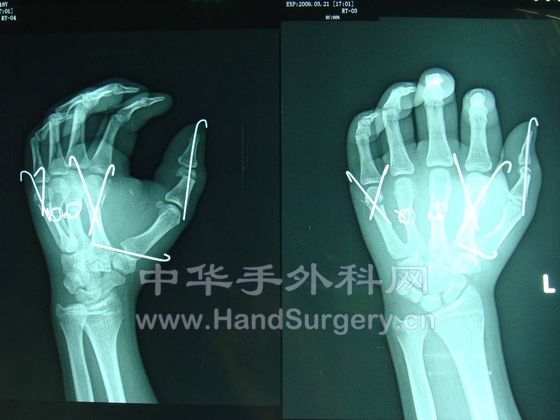

一个断掌+5个断指,显示我科实力!

我这里有术后半年的手术图片,发上来给大家看看,我们曾作出了手外科功能最好的多指离断!

谢谢提醒!我们医院有非常好的康复医师!现在术后27天,已经在逐步进行康复训练了!现在患者右手已经开始自己拿小勺吃饭了!